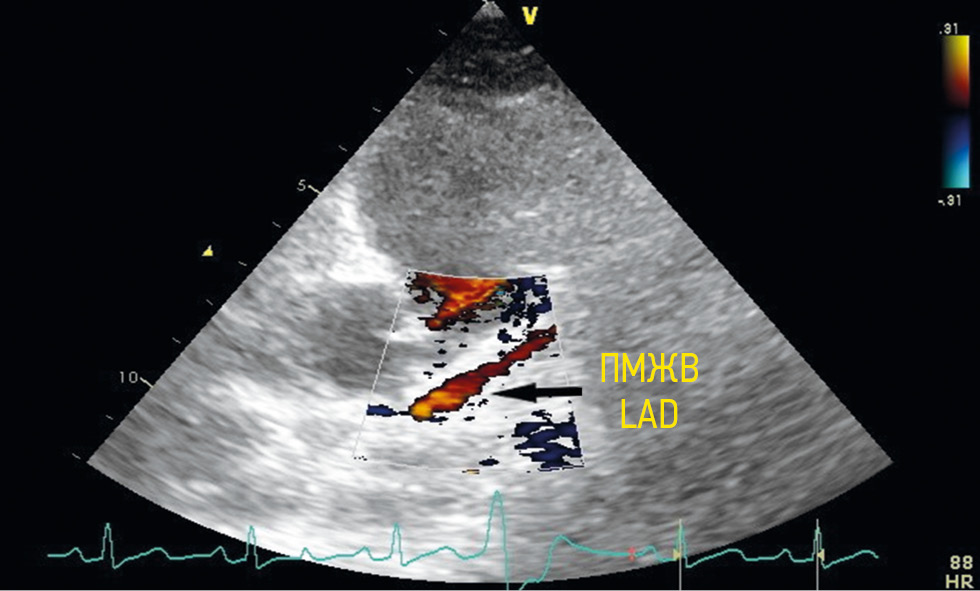

The left anterior descending (LAD) artery was visualized based on the following anatomical features: the anterior interventricular sulcus, the initial origin of the first diagonal artery, and the papillary muscles. A normal antegrade red blood flow was determined by color Doppler imaging. The proximal segment of the LAD was visualized by slightly changing the image plane in the modified left parasternal position along the short or long axis (Figure 2).

Fig. 2. Visualization of the anterior interventricular branch from a modified left parasternal position. LAD — left anterior descending artery / Рис. 2. Визуализация передней межжелудочковой артерии из модифицированной левой парастернальной позиции. ПМЖА — передняя межжелудочковая артерия

The midline LAD segment was visualized from the third or fifth intercostal space in the inferior left parasternal and the modified parasternal positions along the short or long axis of the left ventricle in the anterior interventricular sulcus and the modified apical tricuspid position (Figure 3).

Fig. 3. Visualization of the anterior interventricular branch middle segment from a modified short-axis parasternal position in the anterior interventricular sulcus. LAD — left anterior descending artery / Рис. 3. Визуализация срединного сегмента передней межжелудочковой артерии из модифицированной парастернальной позиции по короткой оси в передней межжелудочковой борозде. ПМЖА — передняя межжелудочковая артерия